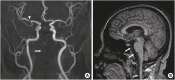

Bilateral cerebral peduncular infarction (BCPI) is a very rare disorder among stroke patients. The main clinical manifestations in the previously reported BCPI case reports was associated with locked-in syndrome or persistent vegetative state. Here, we present a 51-year-old woman who had pseudobulbar palsy and quadriplegia. Magnetic resonance imaging showed an acute infarction in the middle areas of the cerebral peduncle with a unique "Mickey Mouse ears" sign. Diffusion tensor imaging and tractography showed relatively preserved corticospinal tracts, but the corticobulbar tracts were not detected. Magnetic resonance angiography showed posterior cerebral artery and vertebrobasilar artery occlusion. Cerebral perfusion insufficiency due to stenosis or occlusion of the vertebrobasilar artery and its branches may lead to BCPI. The prognosis and clinical manifestations of BCPI are related to the extent of the infarction in the involved cerebral peduncle and whether other territories are involved. Isolated BCPI may present a severe pseudobulbar palsy with relatively preserved limb function depending on the involvement pattern.